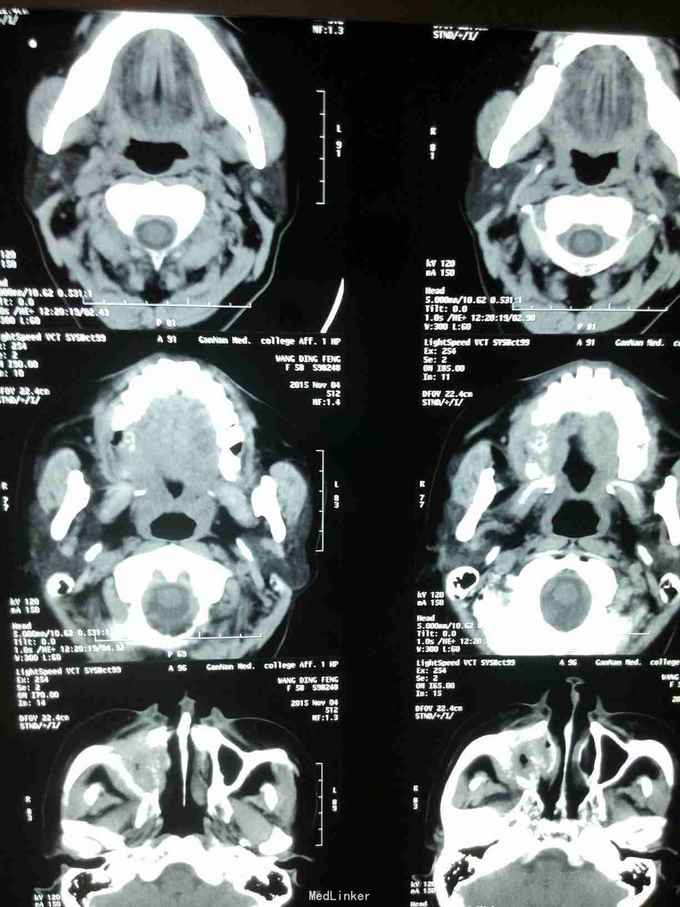

患者女,58岁,因“右上颌后区牙龈溃烂1月”入院 患者于2月前感右上颌后区麻木不适感,一月前在当地医院检查发现上颌后区牙龈溃烂,行抗炎治疗无好转。就诊于我院门诊后行病理检查提示:磷状细胞癌。

查体:心肺腹无明显异常。 专科:右上颌区颊颚侧龈、牙槽脊表面溃烂,凹凸不平,呈不规则溃疡,边缘欠佳。 辅查:CT+三围重建等,见图!

诊断:右上后牙区牙龈磷状细胞癌 治疗:右上后牙区牙龈磷状细胞癌病灶扩大切除+右上颌骨全切+右肩胛舌骨肌上淋巴结清扫术